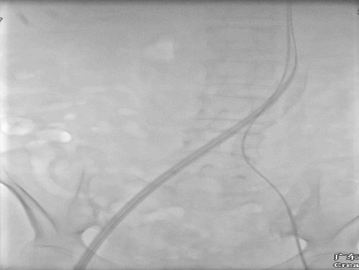

术中DSA:

20F大鞘中DSA发现右股夹层DSA

8*60外周球囊扩张DSA